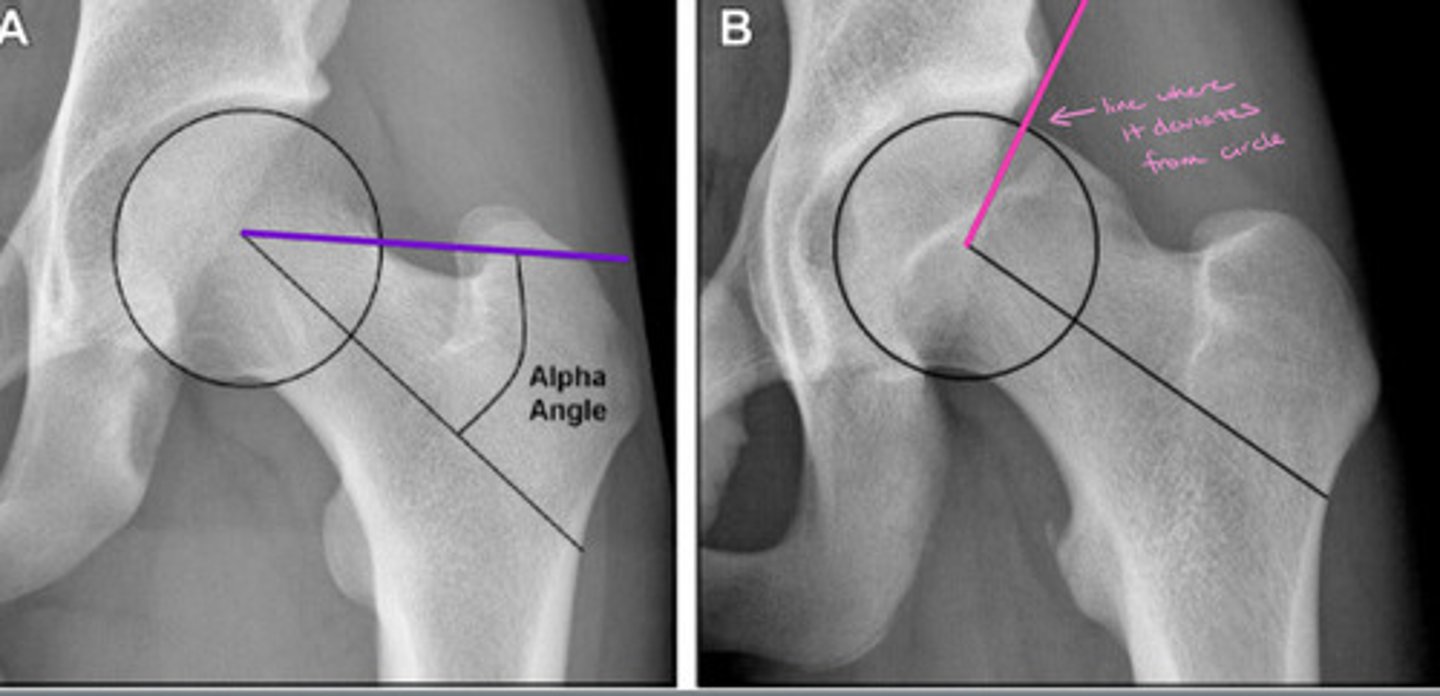

Alpha Angle

Measures the extent to which the femoral head deviates from spherical

Normal = <50 degrees

FAI = >50 degrees